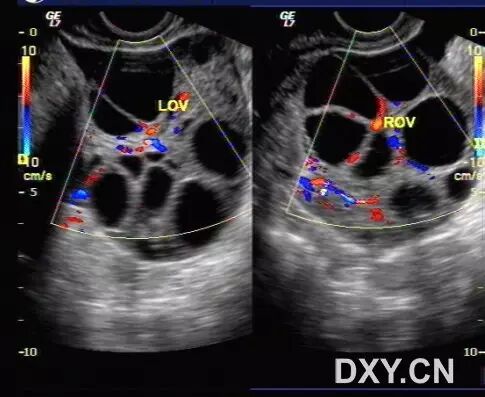

病例2(由丁香园注册用户「荷瓣111」提供):患者女,28岁,结婚5年未孕,应用促排卵药治疗2个月后,自觉腹部膨隆,呼吸困难。

超声所见如下图所示:

图1~3 显示子宫正常,盆腹腔可见两个相依的囊性肿物,其内见多条光带分隔,子宫被压在增大的卵巢下方

图4 显示肝肾区的腹腔积液